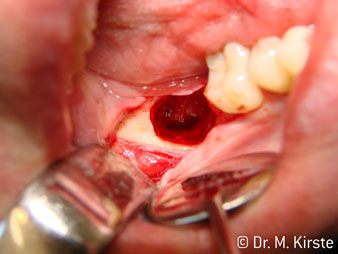

Die Winkelwahl des 45° Handstücks bringt viele Vorteile in der Anwendung. Chirurgisch tätige Kollegen, und für diese ist das Handstück in erster Linie entwickelt worden, werden schnell bemerken, dass man sehr gezielt arbeiten kann. Insbesondere bei der Weisheitszahnentfernung (Abb. 2) bedarf es keiner großen Weichteilabspreizungen im Wangenbereich (Abb. 3). Die Handstückkopfgestaltung kombiniert mit leichten Kopfdrehungen bei der Präparation lassen ein sicheres und schnelles Arbeiten im retromolaren Bereich zu.

Die professionelle Lagergestaltung im Innenleben des Handstückkopfes garantiert einen ruhigen Lauf der Bohrer, bei der Zahn- oder Wurzelseparation (Abb. 4 - 9) zeigt sich ein beeindruckendes Schnittbild ohne Schlageffekte.

Abb. 2

Abb. 3

Abb. 5

Abb. 4

Abb. 6

Abb. 8